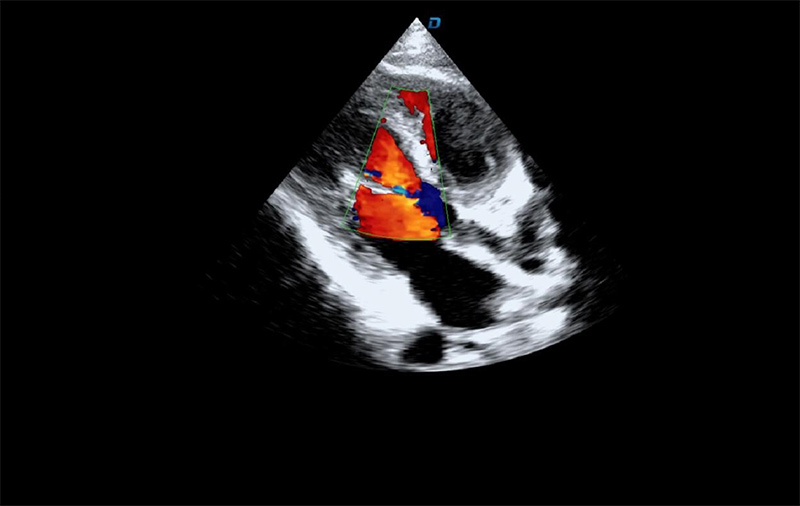

有些心臟病會引起心臟電活動的改變,但是有些心臟的疾病卻不影響心電,而只影響心臟本身的結構。比如心臟擴大,心臟收縮無力,心臟的瓣膜關閉不嚴密,這些疾病的診斷及發現更多的依賴于心臟彩超,這些病變一般不隨癥狀的緩解而緩解。心臟超聲心動圖,不需要開胸,就可以看到心臟的大小、內部結構、瓣膜運動情況等。除了探頭壓迫可能會有疼痛或不適感外,對患者沒有任何創傷。

臨床上,心臟超聲心動圖主要用于對各種先心病、心臟瓣膜病的診斷;各種心肌病、心包疾病的診斷和心臟功能的評估。部分嚴重肺氣腫、胸廓畸形等患者,因為超聲圖像質量欠佳而診斷效果受到一定限制。

大為T8心臟彩超機

心臟彩超機檢測圖